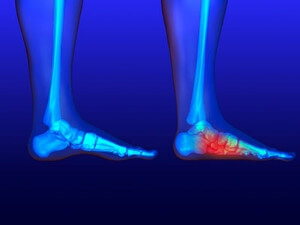

Stress fractures develop when a bone that’s constantly under stress eventually weakens. It typically occurs on the outside of the bone and happens due to repetitive motion. Many professional athletes and runners develop this condition, as overuse of the bones in the foot is common. The way the foot is structured may be another cause, as having flat feet or higher arches may be a contributing factor in developing stress fractures. When overdoing a specific activity, the risk is high for developing these fractures. There may not be physical signs and symptoms from the fracture, but when the activity resumes, pain is often felt. An x-ray is used to determine exactly where the fracture is. Recovery comes from resting the foot and being careful not to put stress on the bones. Occasionally a medical boot is worn to keep the fracture from worsening, in addition to engaging in physical therapy. Please seek the advice of a podiatrist if you feel you have a stress fracture in the foot or ankle.

Stress fractures develop when a bone that’s constantly under stress eventually weakens. It typically occurs on the outside of the bone and happens due to repetitive motion. Many professional athletes and runners develop this condition, as overuse of the bones in the foot is common. The way the foot is structured may be another cause, as having flat feet or higher arches may be a contributing factor in developing stress fractures. When overdoing a specific activity, the risk is high for developing these fractures. There may not be physical signs and symptoms from the fracture, but when the activity resumes, pain is often felt. An x-ray is used to determine exactly where the fracture is. Recovery comes from resting the foot and being careful not to put stress on the bones. Occasionally a medical boot is worn to keep the fracture from worsening, in addition to engaging in physical therapy. Please seek the advice of a podiatrist if you feel you have a stress fracture in the foot or ankle.

Activities where too much pressure is put on the feet can cause stress fractures. To learn more, contact one of our podiatrists from New Jersey Foot & Ankle Centers. Our doctors can provide the care you need to keep your pain free and on your feet.

Dealing with Stress Fractures of the Foot and Ankle

Stress fractures occur in the foot and ankle when muscles in these areas weaken from too much or too little use. The feet and ankles then lose support when walking or running from the impact of the ground. Since there is no protection, the bones receive the full impact of each step. Stress on the feet can cause cracks to form in the bones, thus creating stress fractures.

What Are Stress Fractures?

Stress fractures occur frequently in individuals whose daily activities cause great impact on the feet and ankles. Stress factors are most common among:

- Runners

- People affected with Osteoporosis

- Tennis or basketball players

- Gymnasts

- High impact workouts

Symptoms

Pain from the fractures occur in the area of the fractures and can be constant or intermittent. It will often cause sharp or dull pain with swelling and tenderness. Engaging in any kind of activity which involves high impact will aggravate pain.

If you have any questions please feel free to contact our office located in Oradell, NJ . We offer the newest diagnostic and treatment technologies for all your foot and ankle needs.